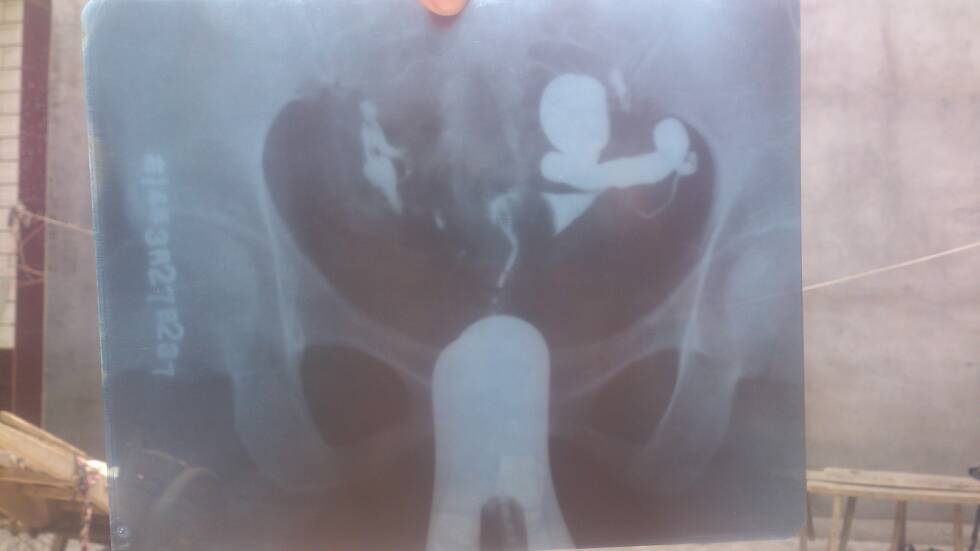

帮忙看看输卵管造影图像,刚才提问上传过一张照片了,不知道怎么上传两张,麻烦医生看看,好人好报!谢谢 点击展开 匿名用户 2014-04-08 12:27 为您推荐: 其他回答 病情分析: 由于每个医院的实验设备, 指导意见: 试剂不同,正常参考值也有一定的差异,你的检查结果,建议咨询你的经治医生。 种凌丝_IyuJ 2014-04-08 13:58 相关问题 最新输卵管造影图片,麻烦各位大侠帮忙看看,纠结中 输卵管造影 请懂的人帮忙看看怎么办?谢谢了 输卵管造影检查结果麻烦大家帮忙看看